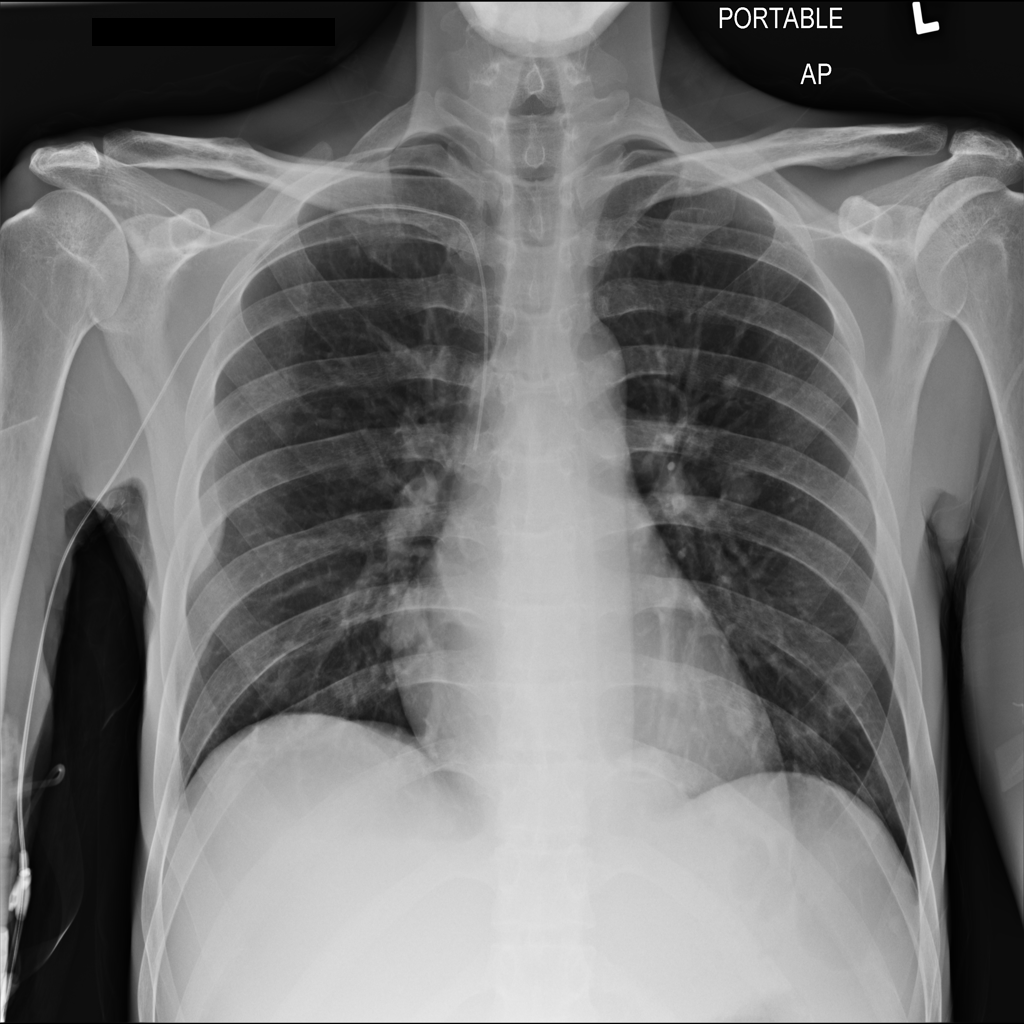

PAT-C048 · IMG-000Hernia

PAT-C048 · IMG-000

PA